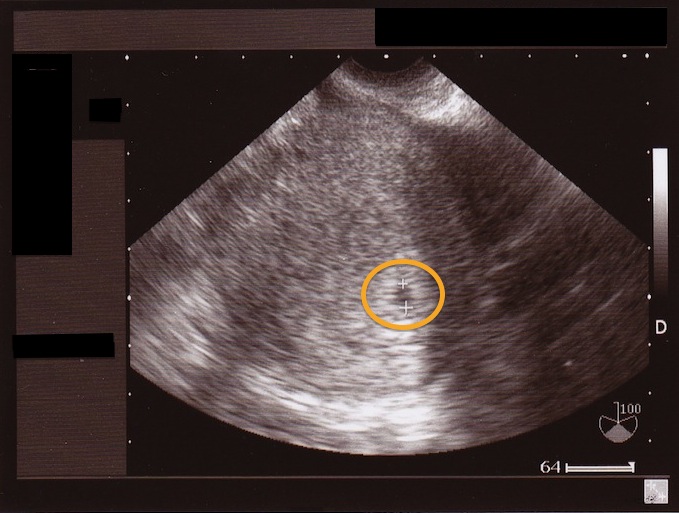

妊娠5週 エコー写真

妊娠5週 エコー写真. 遅くても5週の始めには、胎嚢を確認できるようになります。大きさは14㎜程(9~mm)です。 参考記事 妊娠5週目 胎嚢のエコー写真・つわり症状や流産のこと 妊娠6週目の胎児の発達・エコー写真. 赤ちゃんの超音波、エコー写真。妊娠週ごとに掲載されているので、あなたのエコー写真と比べてみては? 2d、3d、カラー超音波など種類もさまざまですね。(エコー写真の保存) 妊娠中のエコー写真 見たい妊娠月にジャンプ↓. 妊娠5週3日(5w3d)の赤ちゃんのエコー写真です。投稿も募集しています。 生理周期が28日であれば、6週4日ですが、 胎嚢の大きさからエコー写真に5週3日と計算されてますね。 前回8週で心拍確認後に流産しているので、とても不安ですが 胎嚢は18mmで.

妊娠5週6日目のエコー写真と胎嚢の大きさ&費用 妊娠5週6日目のエコー写真と胎嚢の大きさ↓↓ 胎嚢(GS)は、143mmで 前回受診時(妊娠4週5日目)のときよりも大きくなっていました!!. 妊娠5週6日目のエコー写真と胎嚢の大きさ&費用 妊娠5週6日目のエコー写真と胎嚢の大きさ↓↓ 胎嚢(GS)は、143mmで 前回受診時(妊娠4週5日目)のときよりも大きくなっていました!!.